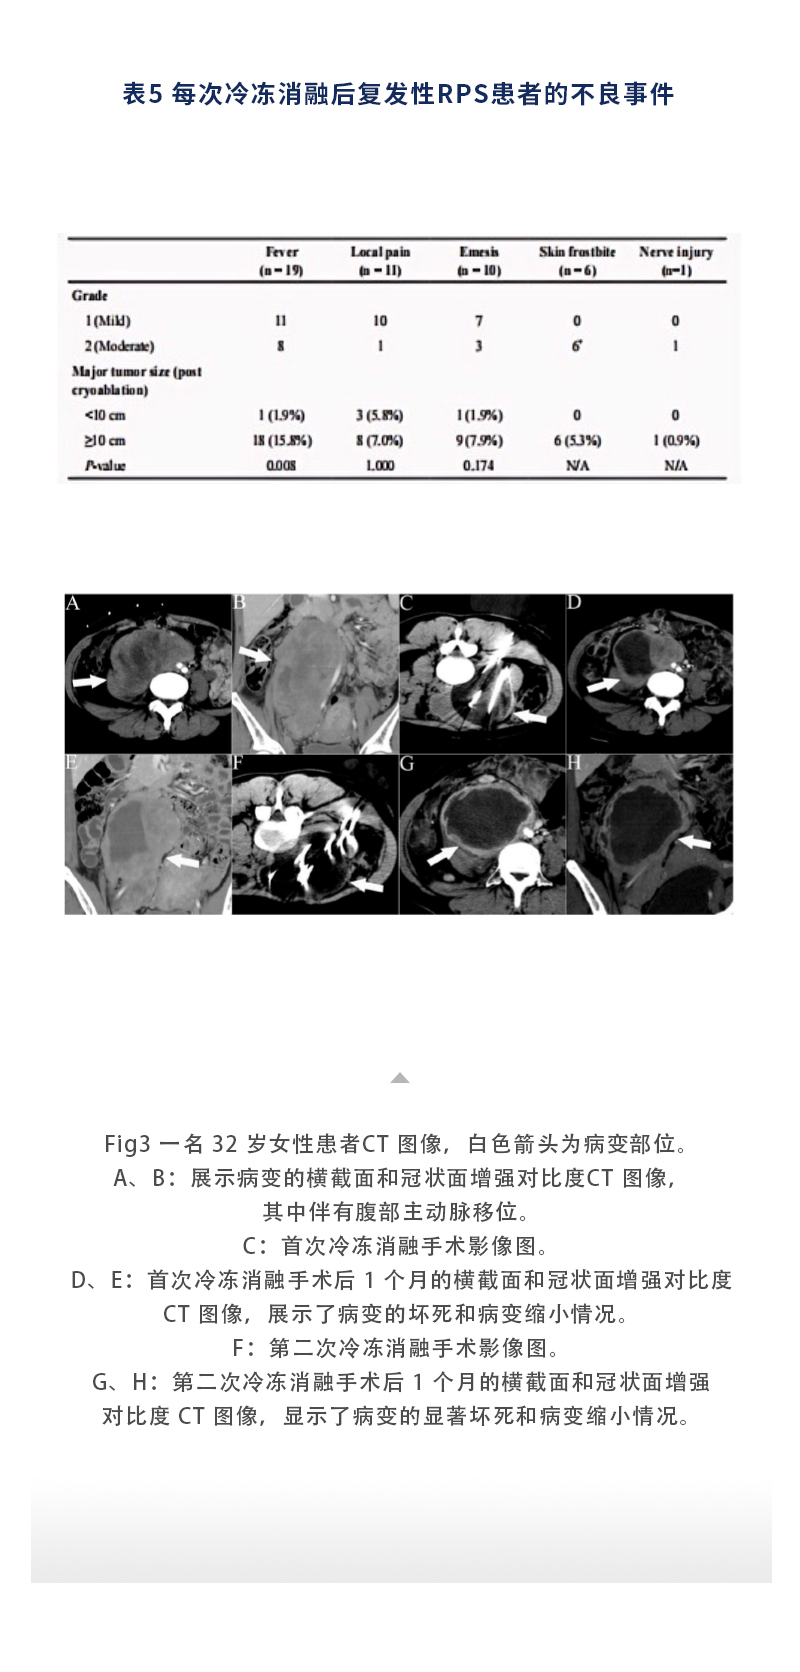

上一頁(yè):【HYGEA·科研資訊】骨腫瘤冷凍消融